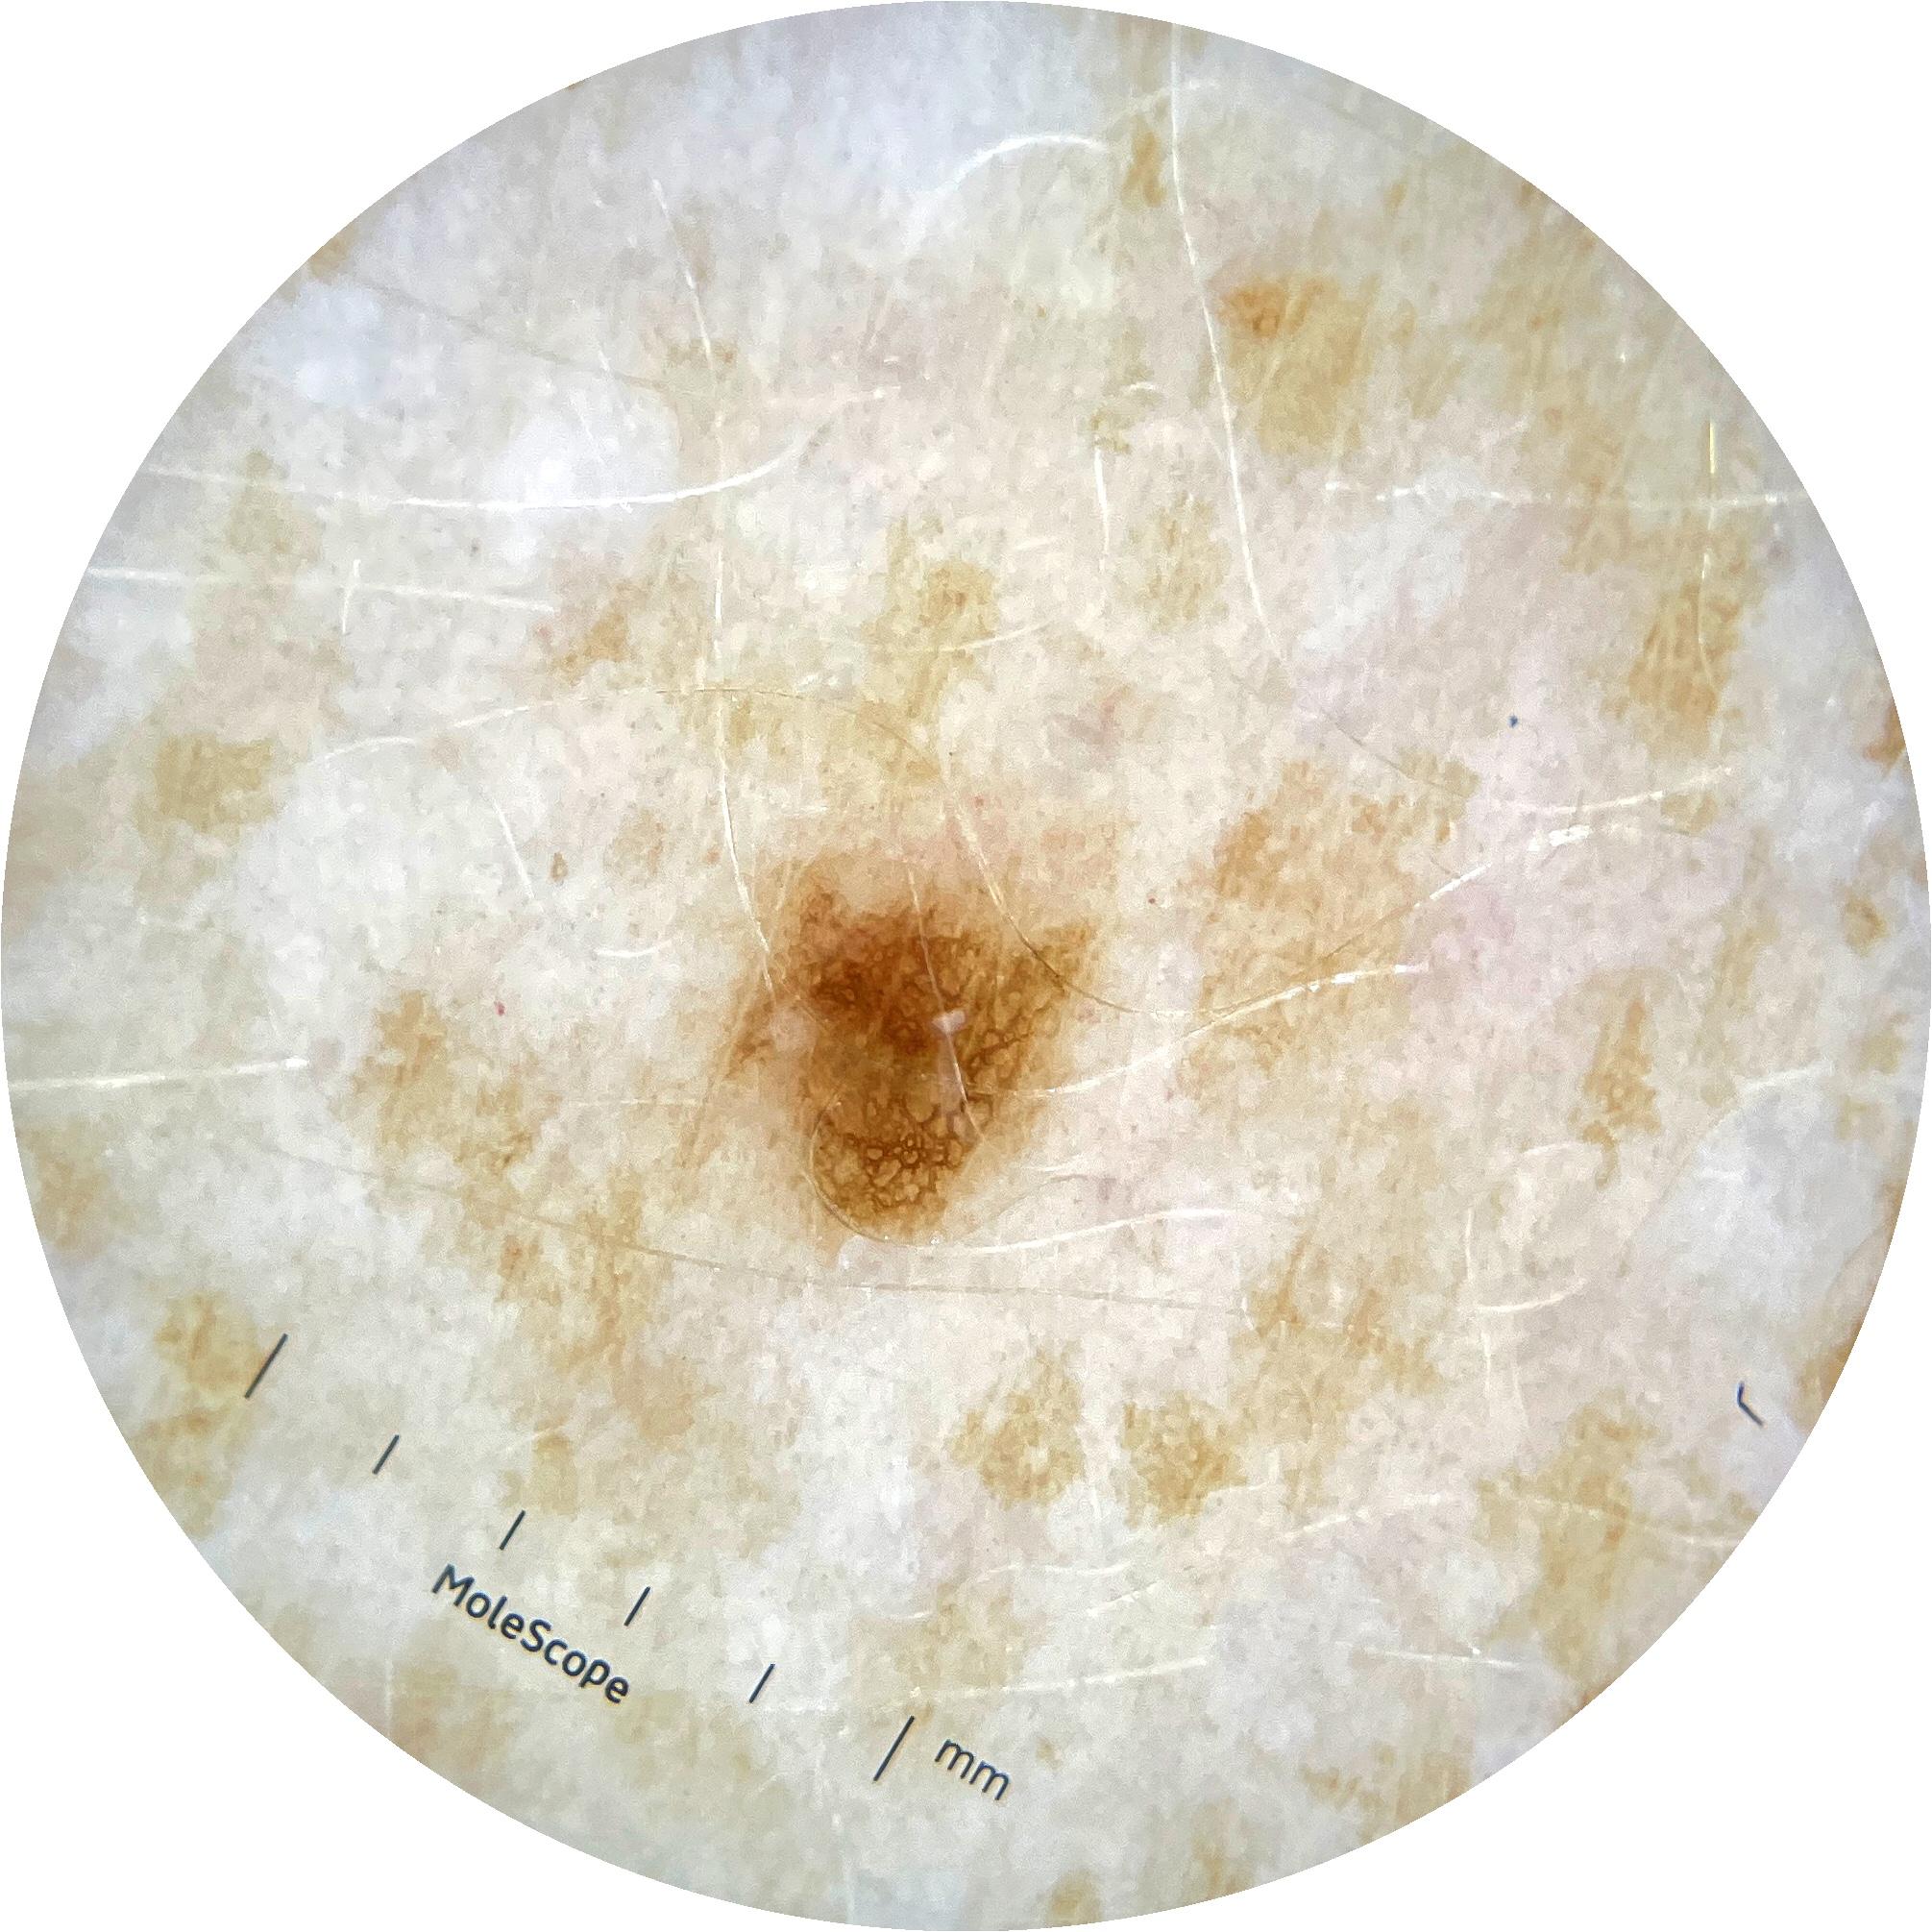

ISIC_9785574

2003 x 2003

Field Value

acquisition_day 148

age_approx 45

anatom_site_1 Head and neck

anatom_site_general head/neck

concomitant_biopsy False

diagnosis_1 Benign

diagnosis_confirm_type single image expert consensus

family_hx_mm True

image_manipulation instrument only

image_type dermoscopic

lesion_id IL_0236417

patient_id IP_8456088

personal_hx_mm True

sex female